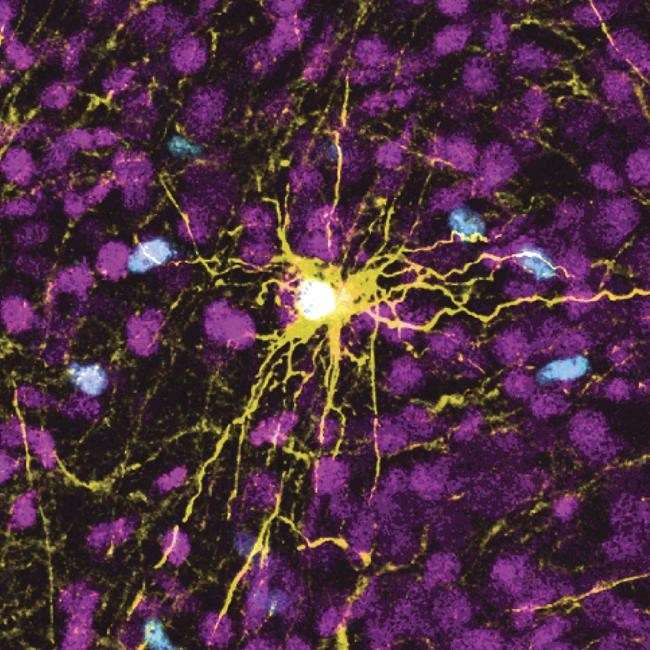

To make the brain organoids, Stanford University scientists transformed human skin cells into stem cells and then coaxed them to become several types of brain cells. Those cells then multiplied to form organoids resembling the cerebral cortex, the human brain’s outermost layer, which plays a key role in things like memory, thinking, learning, reasoning and emotions.

Scientists transplanted those organoids into rat pups 2 to 3 days old, a stage when brain connections are still forming. The organoids grew so that they eventually occupied a third of the hemisphere of the rat’s brain where they were implanted. Neurons from the organoids formed working connections with circuits in the brain.

Human neurons have been transplanted in rodents before, but generally in adult animals, usually mice. Pasca, a psychiatry professor at the Stanford School of Medicine, said this is the first time these organoids have been placed into early rat brains, creating “the most advanced human brain circuitry ever built from human skin cells and a demonstration that implanted human neurons can influence an animal’s behavior.”